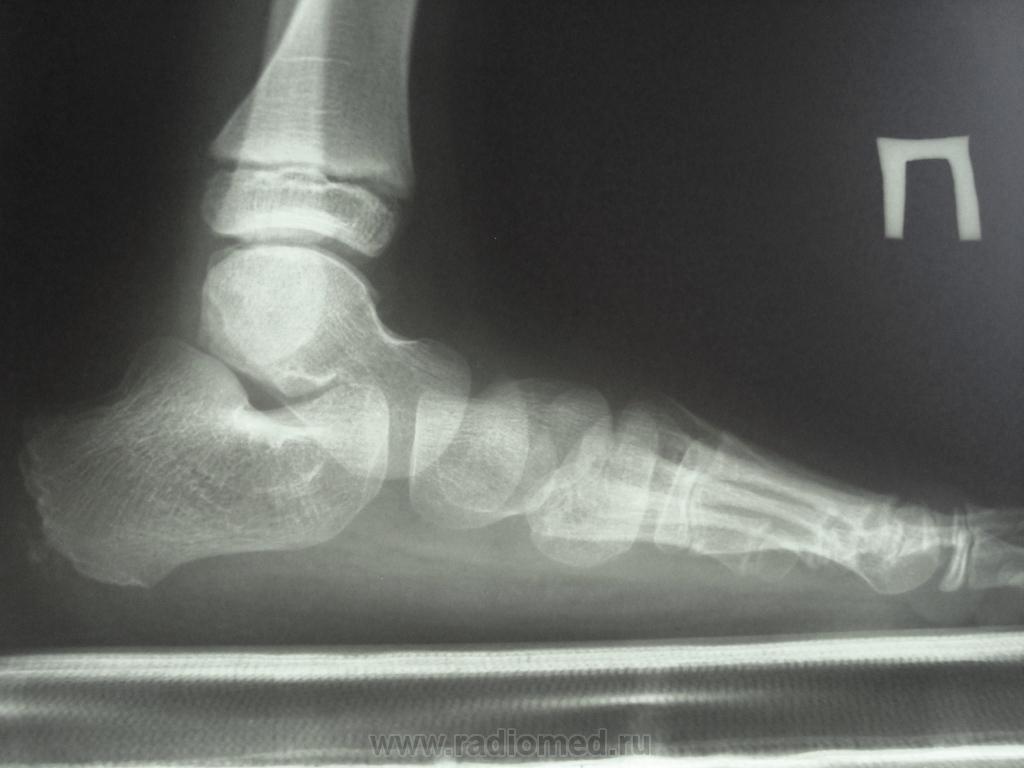

Углы свода, определяемые на профильной рентгенограмме стопы: а - ладьевидный угол свода; б - угол наклона пяточной кости; в - угол наклона переднего отдела; г- таранно-пяточный угол; д - высота костного свода

Для оценки положения костей заднего и переднего отделов определяют угол наклона пяточной кости (угол между касательной к подошвенной поверхности пяточной кости и линией плоскости опоры), который в норме колеблется в пределах 15-20°, и угол наклона переднего отдела стопы (угол между касательной к подошвенной поверхности I луча (I плюсневой, I клиновидной и ладьевидной костей)) - к линии плоскости опоры, достигающий в норме 25°, а также таранно-пяточный угол, который образуется в месте пересечения осевых линий таранной и пяточных костей и составляет в норме 30°.

Угол продольного свода (про который я говорила) в норме 120-125 градусов. Измерьте. По снимкам видно, что плоскостопие есть. Таранные кости не должны быть так расположены, сильно головки опущены. А пяточно-подошвенный угол правильно измерили?

Это Вы расчертили угол продольного свода. А пяточно-подошвенный не так расчерчивается - первая линия - соединяет нижнюю точку пяточного бугра и нижнюю точку головки первой плюсневой кости, вторая линия - касательная к нижней поверхности пяточной кости.

Вроде все верно))). По углу свода дела похуже, этот угол применяется при деформации стоп, в частности, при плоско-вальгусной, в норме он 120-125 гр, при легкой степени деформации увеличивается до 140 гр, при средней ст - до 160, при тяжелой еще больше.

У данного ребенка очень сильно опущены головки таранных костей. У нас таких детей оперируют, делают внесуставной подтаранный артродез.

готово, проверьте!!!!справа угол свода 155 гр, слева 160. Пяточно-подош справа 15, слева 13. Получается плоскостопие 1ст.